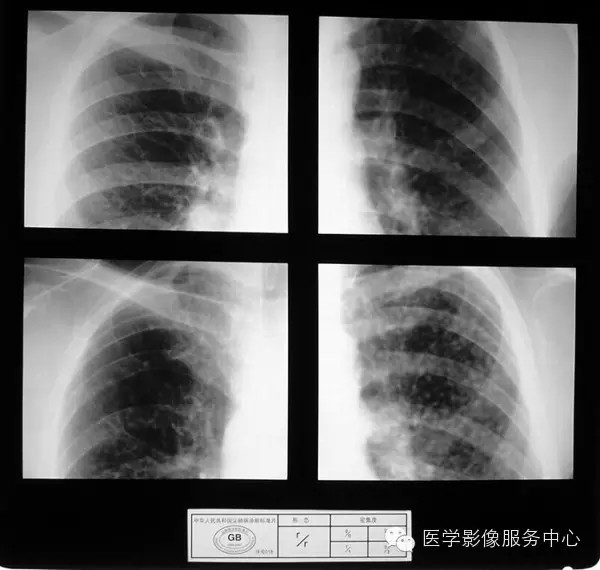

4.4 三期尘肺(Ⅲ)

a)Ⅲ:有大阴影出现,其长径不小于20mm,短径不小于10mm。

b)Ⅲ :单个大阴影的面积或多个大阴影面积的总和超过右上肺区面积者。